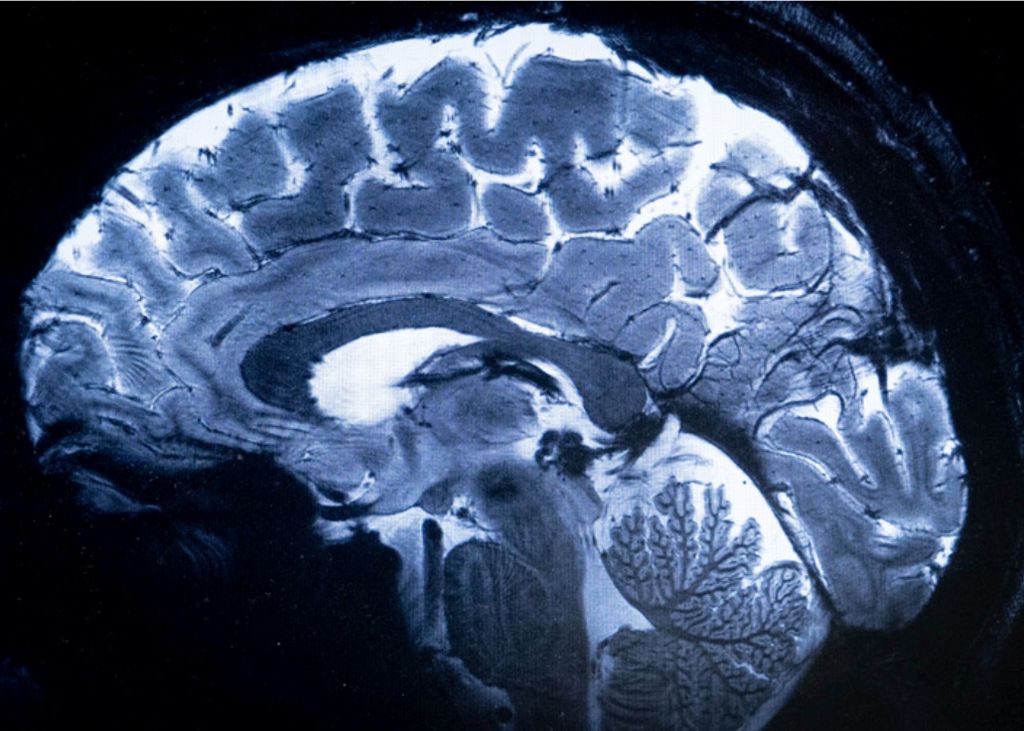

Este resonador puede obtener imágenes con una potencia de 11,7 Teslas, logrando mucha mayor nitidez en comparación con los RM habituales que logran una potencia de hasta tres teslas.

Según Alexandre Vignaud, físico del proyecto, este escáner, llamado Iseult, ha alcanzado un nivel de precisión nunca antes visto en el CEA. Con un campo magnético de 11,7 teslas, diez veces más potente que los RM convencionales, la máquina puede capturar detalles sorprendentes que anteriormente eran casi invisibles. Esto incluye la visualización de pequeños vasos sanguíneos que alimentan la corteza cerebral y detalles del cerebelo.El avance de esta tecnología promete mejorar significativamente la capacidad de diagnóstico y comprensión del cerebro humano, lo que podría tener importantes implicaciones en el campo de la medicina y la neurociencia.